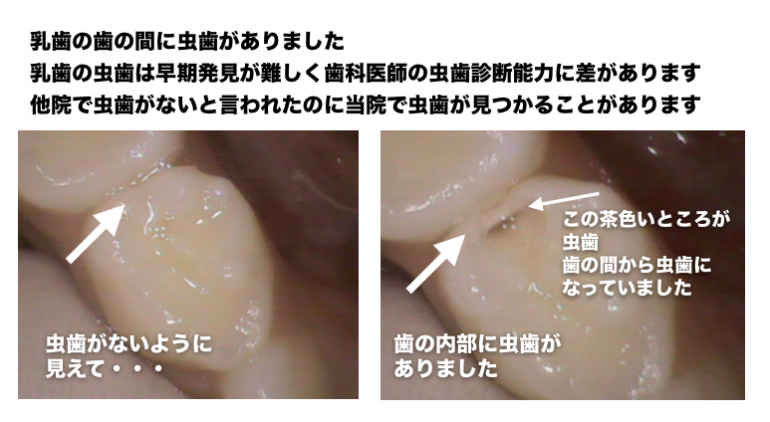

歯科医師によりレントゲンから虫歯を判断する能力(技術)には差があります

当院では、虫歯診断能力のある歯科医師が在籍しているため、適切な診断をし治療をしています

CASE3

CASE4